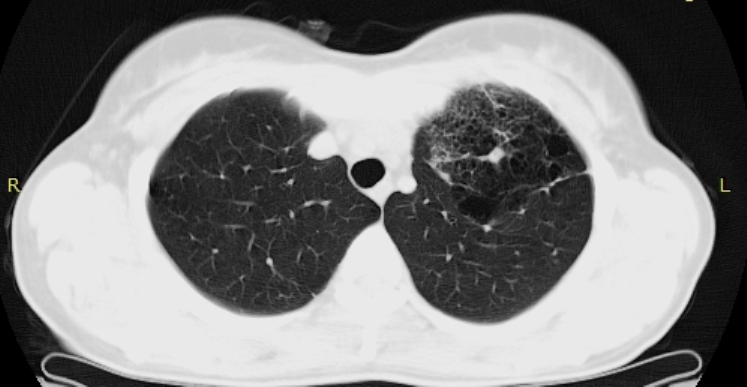

Женщина 35 лет. Жалоб нет. Профилактическая ФГ - дополнительная тень у головки левого корня (снимок пленочный, маленький...не переснимал, так как вряд ли удасться добиться хорошего качества). Подняты пленочные ФГ за 2009 и 2010 гг - есть небольшая деформация легочного рисунка и просветления без четкой контурации у левого корня (естественно - все это ретроспективно, с учетом уже известной информации).

Это НЕ "сотовое легкое"

Отправлять на нормальную КТ с контрастом. Думаю, будет аномалия сосудов, дисгенезия легкого слева. Представленных картинок явно недостаточно, нужны сканы в средостенном окне с контрастом.

Можно подумать  об артерио-венозной мальформации.Тем более имеются характерные изменения в окружающей лёгочной ткани и прилежащих бронхах. Конечно, нужно контрастировать.

Явно аномалия, нет сомнений. Но секвестрация сомнительна, хотя....

Пока, без Дайкома, можно предположить БЭЛ (локальную).

БЭЛ: Буллезная эмфизема легких. Причины: от воспалительных процессов до врожденных ферментативных нарушений.

имхо:скорее всего гипогенезия верхней доли левого лёгкого  с  буллезно-фиброзными проявлениями.